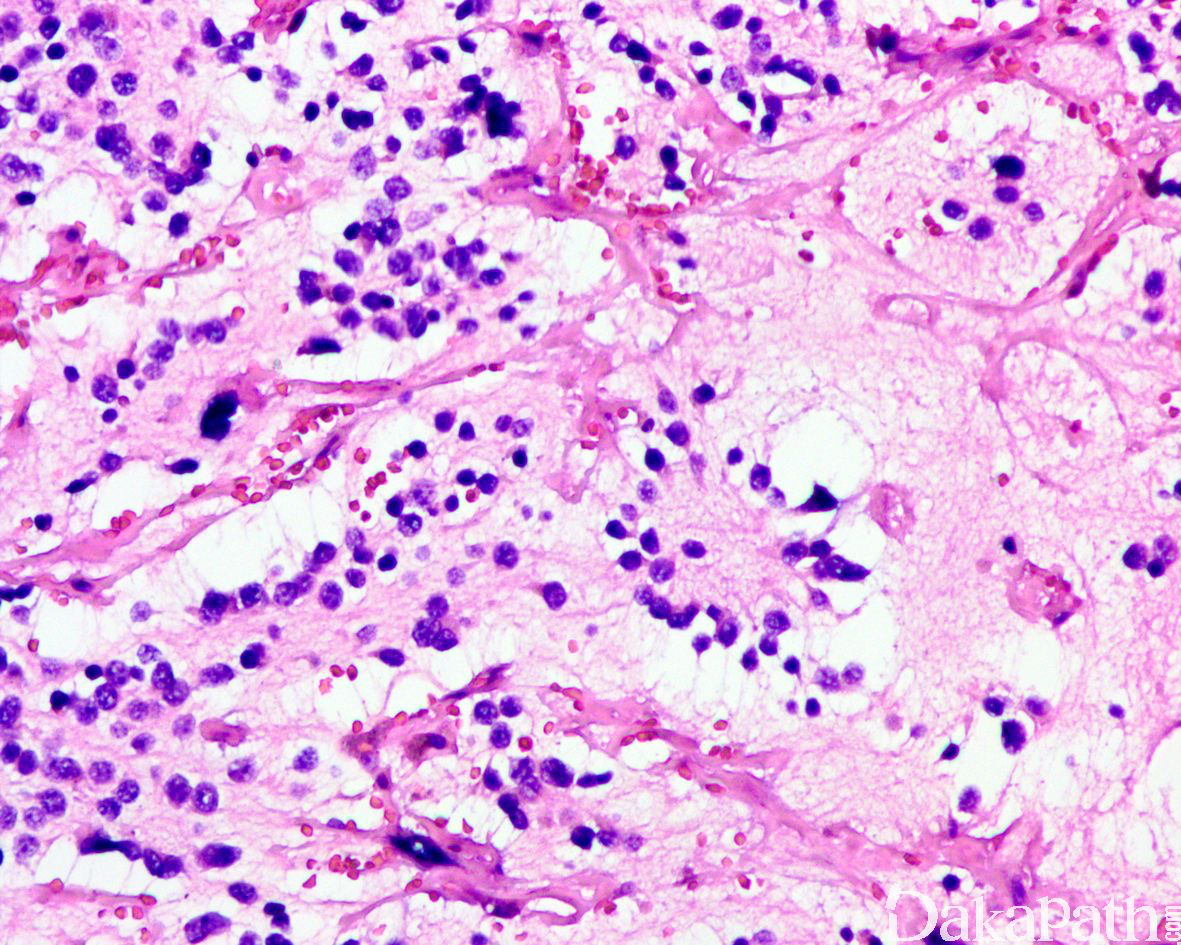

瘤细胞小而一致,胞浆稀少,染色质细腻,核仁不明显,核分裂象较活跃;神经节细胞分化< 5%,神经节细胞分化定义为瘤细胞的胞体和胞核同时增大,细胞的直径 2 倍或以上于核的直径(诊断神经节细胞分化所必须),可见丰富的双嗜性胞浆,核偏位伴有空泡状染色质以及明显的核仁;部分细胞表现为未分化神经母细胞瘤和成熟的神经节细胞之间的过渡状态,表现为瘤细胞核轻度增大伴有开放的染色质和明显的核仁;

瘤细胞核染色质呈粉尘状或点彩状,神经节细胞分化< 5%;

偶见体积较大、异型性较明显的瘤细胞伴有开放的染色质和显著的核仁,少数可表现为 Rhabdoid 的胞浆特征;